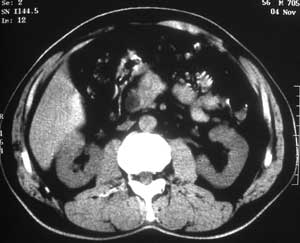

患者,男,57岁,梗阻性黄疸10余天。

这个病例胰头无明显增大,胆总管扩张明显而肝内胆管扩张更不明显,病程较短,

注意到十二指肠乳头明显突出,但尚光滑。分析以下可能性:

1、十二指肠乳头本身的病变,如乳头炎症;

2、急性乳头水肿,胆总管下端结石排石后乳头水肿;

3、壶腹部胆总管下端肿瘤累及十二指肠乳头。

十二指肠乳头粘膜慢性非特异性炎症